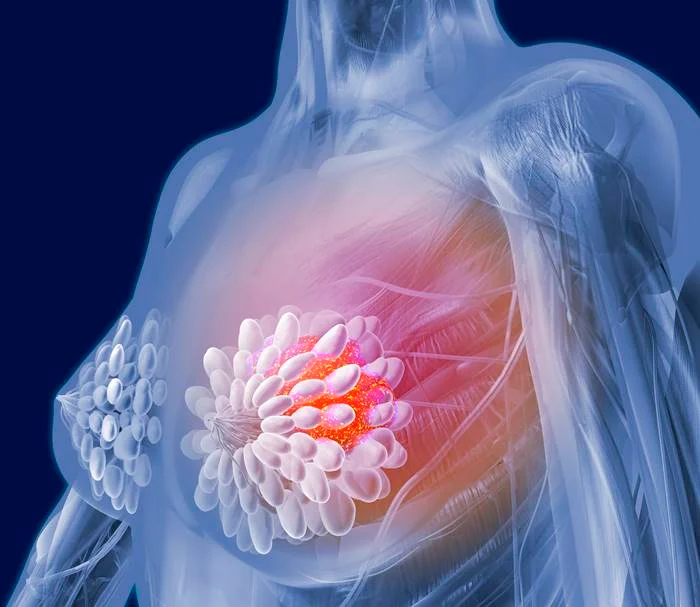

Segundo o Instituto Nacional do Câncer (Inca), há vários tipos de câncer de mama. Alguns têm desenvolvimento rápido, enquanto outros crescem lentamente. A maioria dos casos, quando tratados cedo, apresentam bom prognóstico

Não há uma causa específica para a doença. Contudo, fatores ambientais, genéticos, hormonais e comportamentais podem aumentar o risco de desenvolvimento da enfermidade. Além disso, o risco aumenta com a idade, sendo comum em pessoas com mais de 50 anos

Os principais sinais da doença são o aparecimento de caroços ou nódulos endurecidos e geralmente indolores. Além desses, alteração na característica da pele ou do bico dos seios, saída espontânea de líquido de um dos mamilos, nódulos no pescoço ou na região das axilas e pele da mama vermelha ou parecida com casca de laranja são outros sintomas